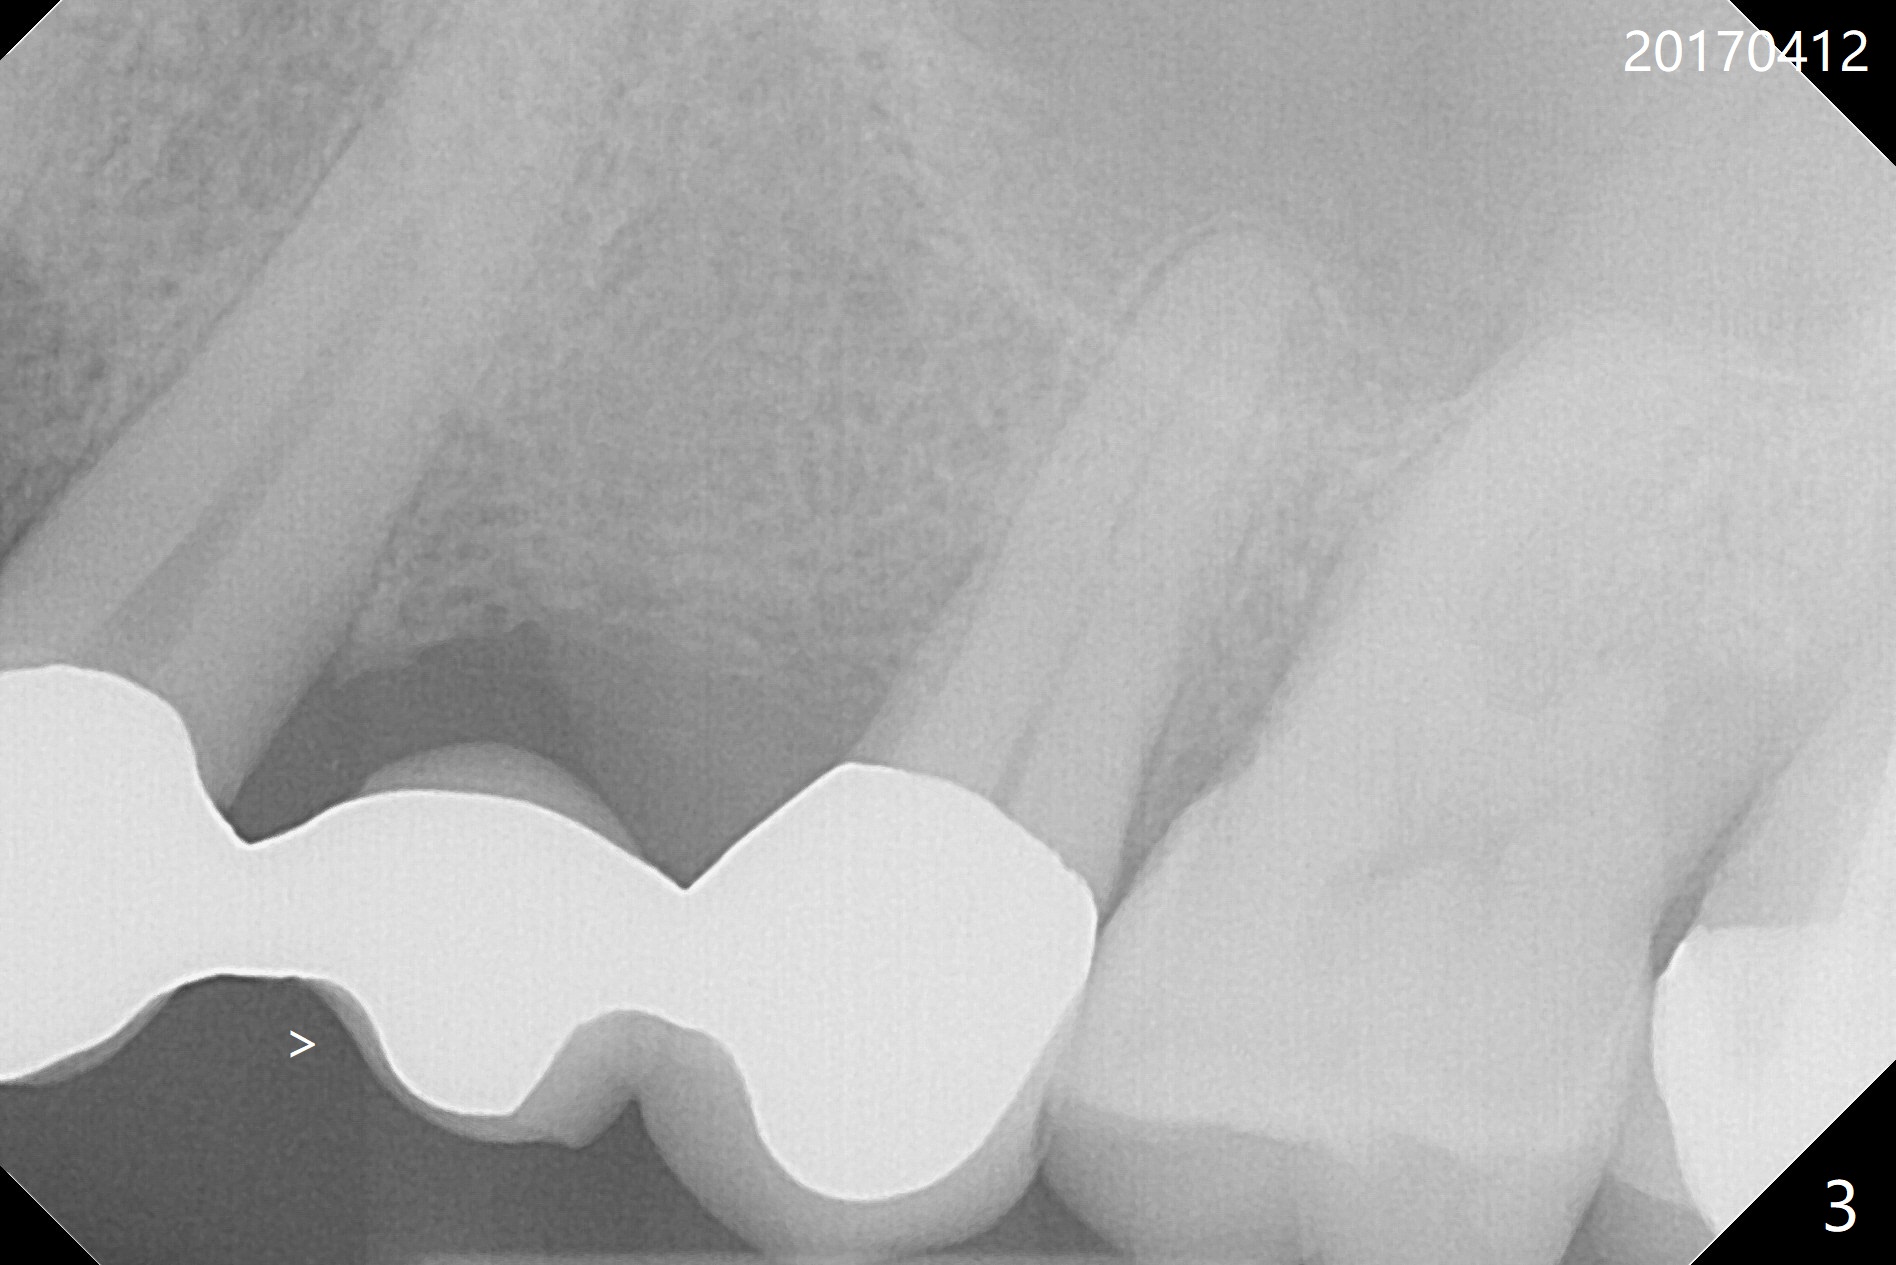

A 71-year-old man finally agrees to have an implant to be placed at #2 four years being our patient. The break point is that the crown at #30 needs recementation. The tooth #2 was missing when he presented for new patient exam (Fig.1,2). The bone loss between #30 and 31 is mild (Fig.1 *) with a small diastema (Fig.2 >). Porcelain chips at the pontic (Fig.3 >). The bone height at #2 is limited (Fig.4). The bone loss and the diastema seem to have got worse in the last 3-4 years (Fig.5). The tooth #15 has mobility with exposure of the buccal roots (Fig.6). Because of bruxism, consider flap surgery to bury the implant at #2 with guide.